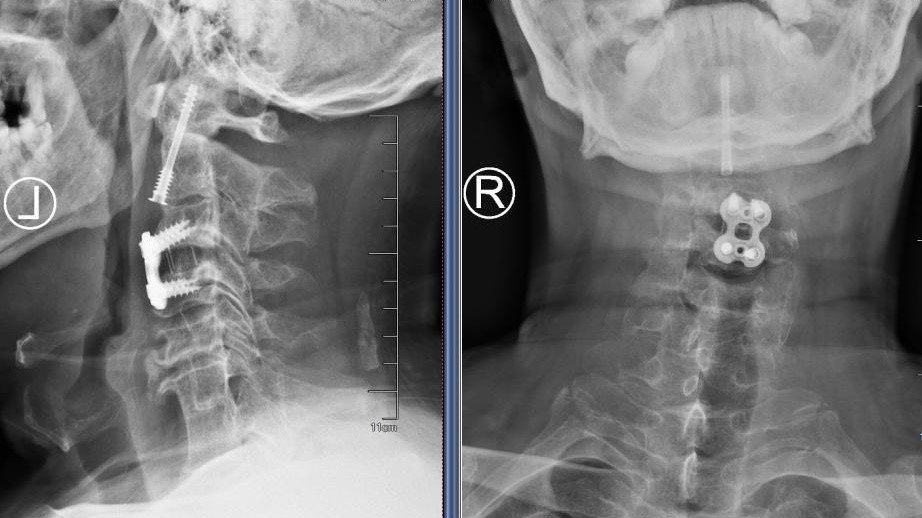

患者侯师傅在工地作业中不幸被坠落的钢筋重重砸中颈部,致使四肢完全无法活动。紧急送医后,查体显示其四肢肌力仅为0-1级,处于近乎全瘫的状态。完善影像学检查提示:枢椎齿状突骨折并向后倾倒,严重压迫脊髓;同时合并有严重的颈椎发育畸形及多处先天性融合。脊髓的严重受损使侯师傅的生命岌岌可危,手术减压固定刻不容缓。

图1:术前CT和MR